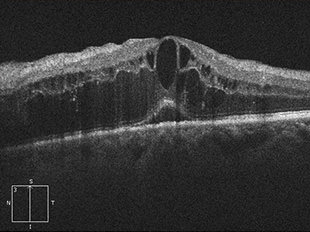

加齢黄斑変性

加齢黄斑変性とは、網膜のほぼ中心部分にあたる特に視機能において重要な部位である黄斑部に、年齢的な変化・変性が生じて起こる病気です。加齢と名のつく通り年配者に多く、近年患者数が急増しており、欧米では失明原因の上位にあげられています。

ものを見る上で特に重要な役割を担う黄斑に障害が起こるため、視野の中心が見えにくい、暗く見える、ものが歪んで見える等、視覚上に症状が出ます。また起こる視力低下の度合いはまちまちですが、矯正視力でも0.1以下という高度の視力障害が起きることもあります。

治療前

治療前 OCT

治療後 OCT